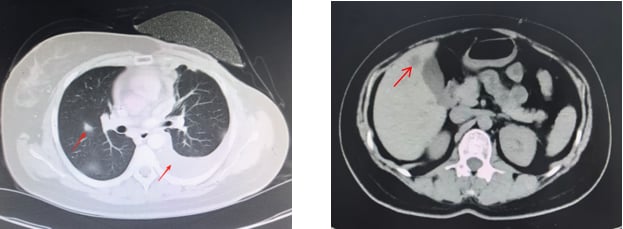

患者接受了规范的初始治疗:手术(左乳单切+SLNB+ALND),辅助化疗(AC-T*8周期),辅助放疗(患侧胸壁+锁骨上下区,50Gy/2Gy/25次),以及内分泌治疗(OFS+来曲唑)。2023年3月,为了强化治疗效果,医生为她加用了阿贝西利进行强化内分泌治疗。然而,尽管进行了积极治疗,疾病的进展依然迅速。2025年1月复查时疾病稳定,但仅两个月后,2025年3月强化内分泌治疗结束后,2025年4月复查就提示肺转移可能。胸部CT、骨扫描、头颅+腰椎CT等影像学检查均显示多发可疑病灶。最终,2025年5月的复查确诊为左乳癌术后肺、肝、左侧胸膜、骨转移,肝脏穿刺病理进一步证实为转移性腺癌,ER表达降至13%中+,PR阴性,HER2(2+),FISH阴性,再次确认HER2低表达。